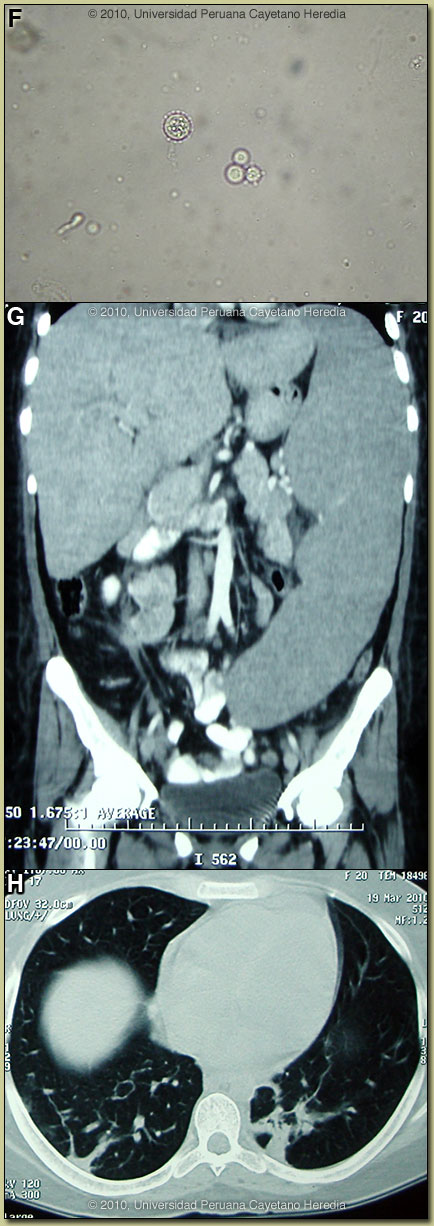

Discussion: Direct KOH preparations of the purulent discharge from the left lacrimal gland, from scrapings of cutaneous lesions and from an aspirate of a cervical lymph node showed spherical cells 10-40 microns in diameter with a thick birefringent cell wall surrounded by several peripheral buds characteristic of Paracoccidioides brasiliensis [Image F]. When completely surrounded by buds a so-called “pilot-wheel” pattern occurs. All cultures were positive for Paracoccidioides brasiliensis. Direct scrapings or aspirates will be positive in the vast majority of cases of paracoccidioidomycosis with cutaneous lesions. Abdominal CT-Scan: non-focal hepatomegaly, massive splenomegaly (24 cm in the longitudinal diameter); and intra-abdominal lymphadenopathy [Image G]. Chest CT-Scan: nodular lesions in both lungs with parenchymal alveolar and interstitial infiltrates [Image H].